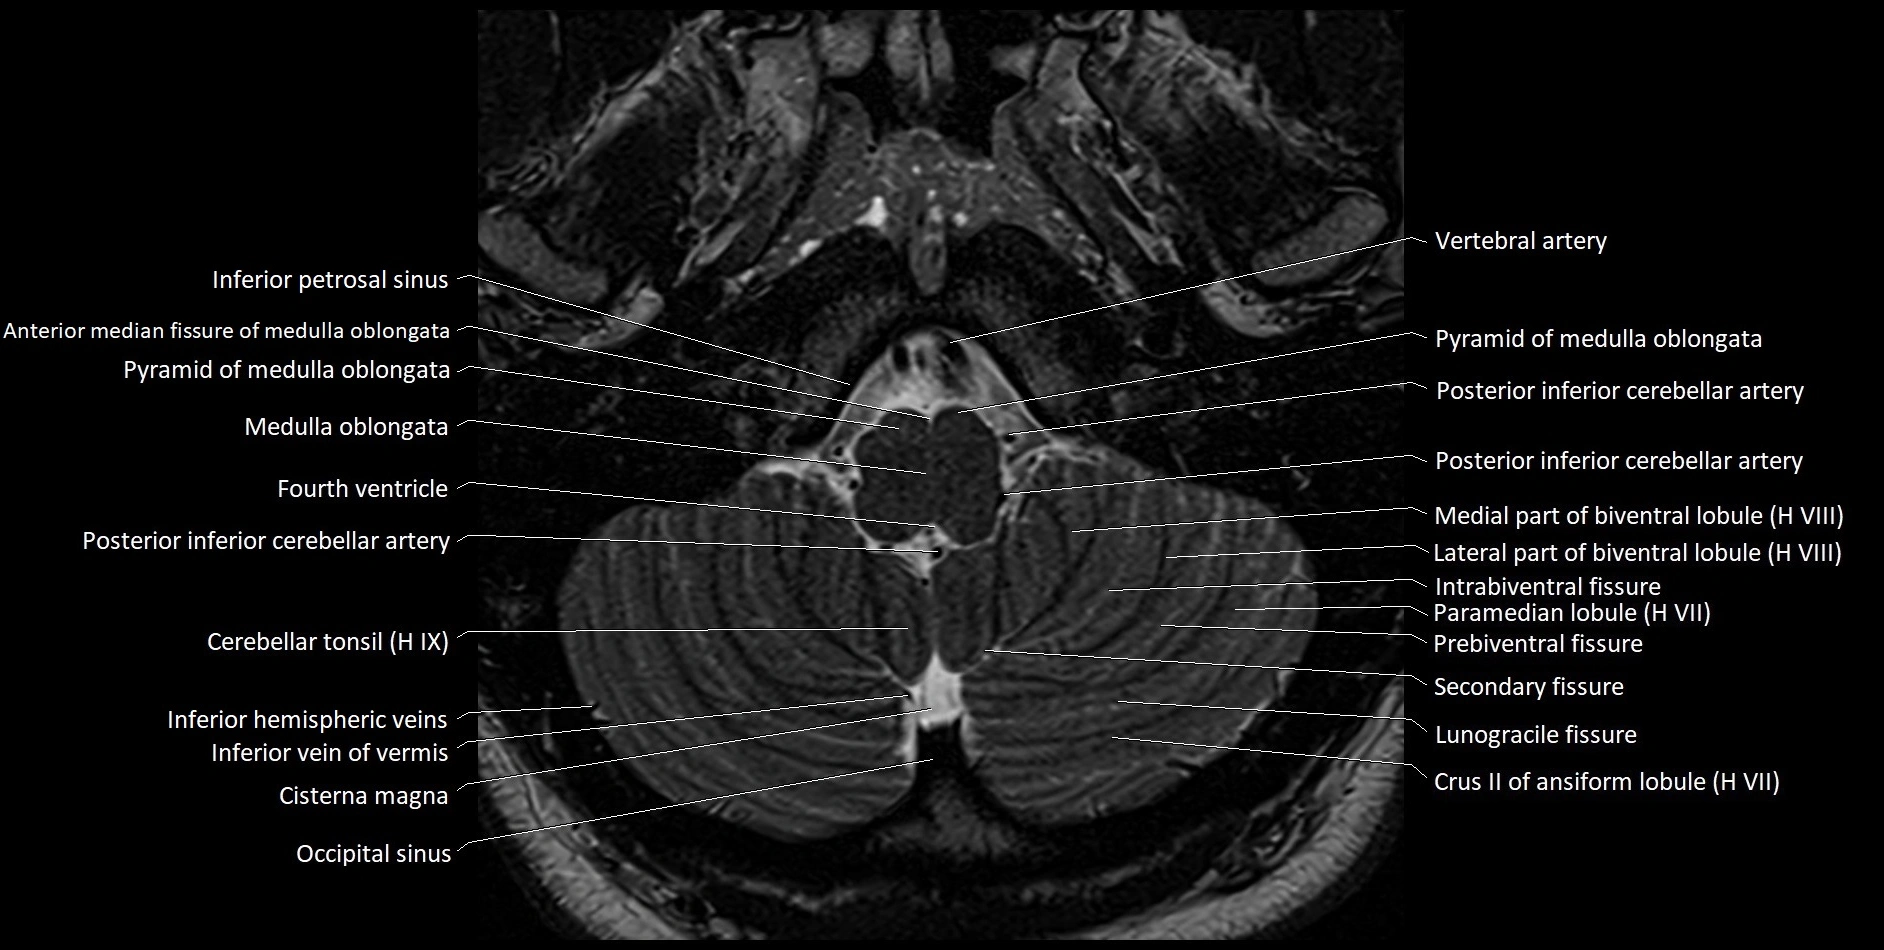

MRI images